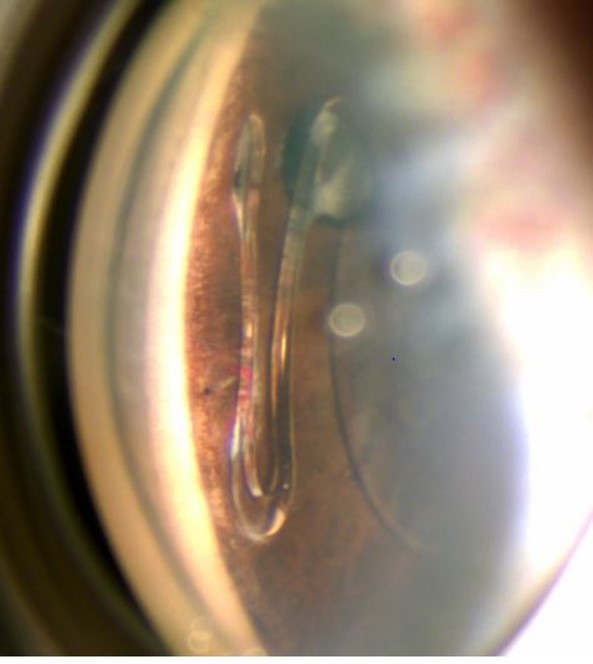

Ophthalmic Photographers’ Society (OPS) 2022 Exhibit

ASCRS and the Ophthalmic Photographers’ Society (OPS) co-sponsor a call for photo submissions of high-quality ophthalmic images demonstrating superior imaging techniques to be selected for the OPS exhibit at the ASCRS Annual Meeting. The photo selection process is highly selective and judged by ophthalmologists and OPS member photographers.

Browse the exceptional 2022 OPS Exhibit winning photos in PDF format by using the link below.